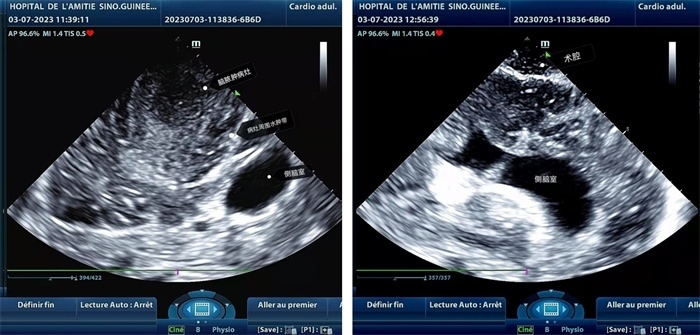

手術(shù)中,張國濱在超聲科顧秀娟的幫助下,運(yùn)用顱腦術(shù)中超聲技術(shù),通過將一次性保護(hù)套的超聲探頭置于腦組織表面,實(shí)時觀察病變的位置和形態(tài),進(jìn)一步確認(rèn)最佳手術(shù)路徑。術(shù)中超聲顯示,病變位于左額頂葉,大小約為4x4x3cm,邊界清晰,呈囊實(shí)性,周邊腦組織水腫明顯。最終,病灶順利切除,診斷為腦膿腫,并通過超聲檢測確認(rèn)術(shù)腔無病變殘留、無出血,為患者術(shù)后恢復(fù)提供了良好的保障。

左圖顯示術(shù)中超聲見囊實(shí)性病變,大小約為4x4x3cm,病灶周圍腦組織水腫明顯;右圖為病灶切除后,術(shù)中超聲示術(shù)腔無病變殘留

左圖顯示術(shù)中超聲見囊實(shí)性病變,大小約為4x4x3cm,病灶周圍腦組織水腫明顯;右圖為病灶切除后,術(shù)中超聲示術(shù)腔無病變殘留。中國第二十九批援幾內(nèi)亞醫(yī)療隊(duì)供圖